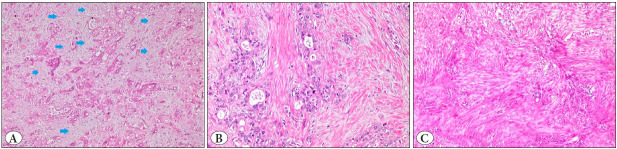

Objective: Pancreatic stellate cells (PSC) have been defined to be the key players in pancreatic fibrogenesis and carcinogenesis. They undergo myofibroblast-like differentiation, express α-smooth muscle actin (α-SMA), and play a crucial role in injury and inflammation sites. This study aims to evaluate the relationship between α-SMA expression and histopathological parameters of pancreatic ductal adenocarcinoma (PDAC), and investigate their association with prognosis.

Material and methods: Eighty-one consecutive pancreatectomies diagnosed as usual pancreatic ductal adenocarcinoma were included. The stromal density was scored as loose, moderate, or dense, and α-SMA expression was evaluated immunohistochemically.

Results and conclusion: Mean survival was 19.6 months. Male gender, larger tumor diameter ( > 3.7 cm), and older age ( > 64 years) were identified as independent poor prognostic factors. Perineural invasion significantly effected survival. A statistically significant correlation was found between high α-SMA expression and the presence of angioinvasion (p=0.01). Stromal α-SMA expression in PDAC may help determine the risk of angioinvasion.